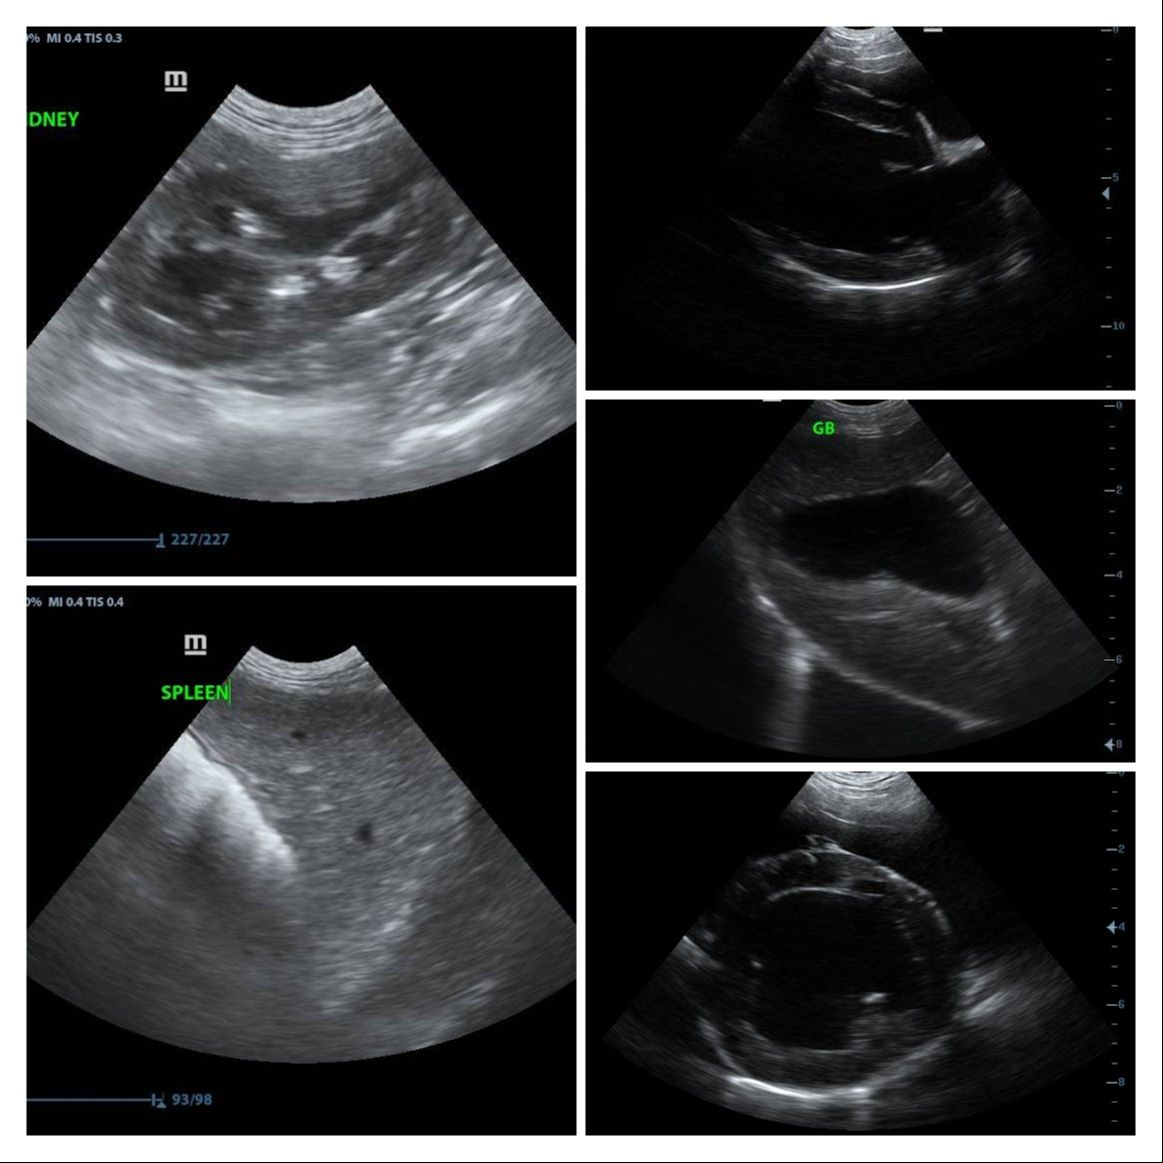

quality was a little disappointing for this price range.

Cons: Image quality.

Image quality ⭐⭐⭐⭐⭐

Images from the Magic P1